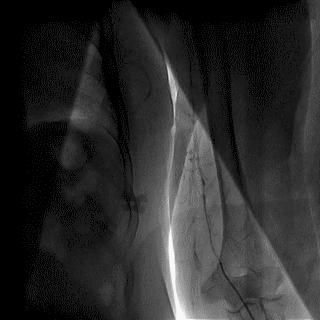

(4)LIMA桥血管造影

首选导管:JR4.0导管

其他导管:如果开口明显成角应选用专用的内乳动脉造影导管

➢ CASE 6

经股动脉途径TIG,非选择造影如果能清晰显影,可不做超选造影

➢ CASE 7

经左侧桡动脉途径JR4.0,非选择造影如果能清晰显影,可不做超选造影